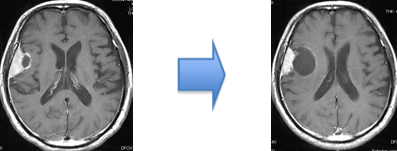

ところが、たとえ腫瘍が小さくても、下の画像に示すように、造影される病変(左)に比べ、脳浮腫(右;白く広がっている部分)が広い範囲に拡大していると、腫瘍の大きさが小さいにも関わらず症状(この場合右足の麻痺やてんかん発作)が重症化することが多いです。腫瘍摘出を行なうと、術後3~4週間で浮腫は消失します。

(術前MRI)

(術後MRI)